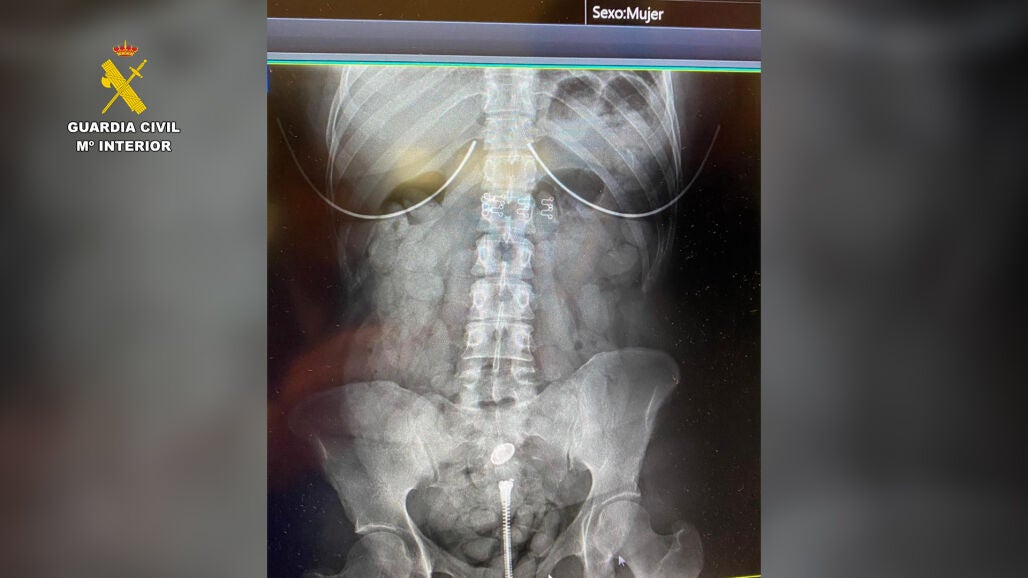

La Guardia Civil ha detenido a tres personas que introducían droga por el aeropuerto de Sevilla, utilizando para ello a una menor para aparentar ser una familia que viajaba como cualquier otra. Una de ellas portaba una faja plástica adosada a su cuerpo con unos 3.000 gramos de bellotas de hachís con un peso aproximado de un kilogramo.

Las bellotas presentaban un tamaño de unos cuatro centímetros y 10 gramos de peso. Las personas implicadas quedaron ingresadas y detenidas en el hospital tras el inminente riesgo de obstrucción intestinal.